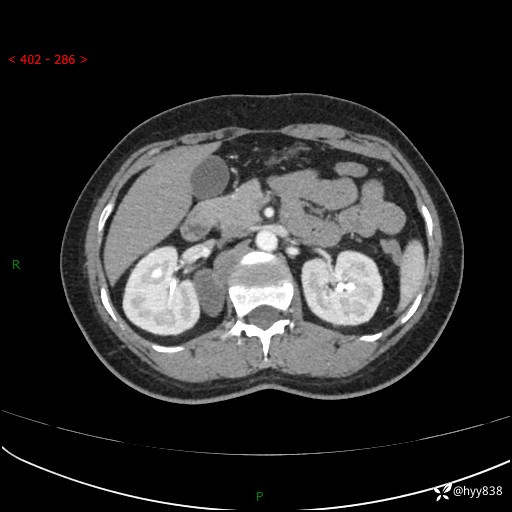

简要病史:患者于1天前因体检发现右旁肾占位,无肉眼血尿,无畏寒发热,无咳嗽咳痰,无腰腹部疼痛不适,无尿频尿急症状,起病来,患者未行特殊治疗,为求进一步诊治,门诊以"右侧腹膜后肿物"收治入院。 发病来患者精神、饮食、睡眠良好,小便如上,大便正常,体重无明显变化。

辅助检查:CT

临床诊断:腹膜后肿物

上腹部CT增强(动脉期+实质期)(外院平扫)